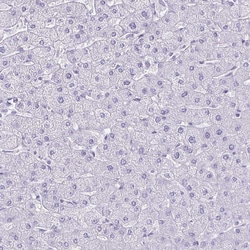

Invitrogen™ ATP4B Polyclonal Antibody

Immunogen sequence: TPDYQDQLRS PGVTLRPDVY GEKGLEIVYN VSDNRTWADL TQTLHAFLAG YSPAAQEDSI NCTSEQYFFQ ESFRAPNHTK FSCKFTADML Highest antigen sequence indentity to the following orthologs: Mouse - 83%, Rat - 80%.

| Immunohistochemistry (Paraffin) | |